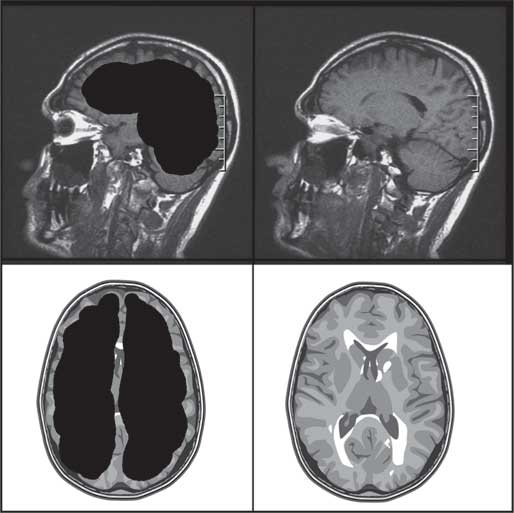

Рис. 1. Слева – мозг Матье (реконструкция), справа – мозг здорового человека

То, что обнаружили специалисты в ходе МРТ-исследования, не укладывалось в представления тогдашней нейронауки. В норме весь череп заполнен серым и белым веществом – это ткань мозга. Внутри есть небольшие цистерны с жидкостью. Но у Матье отсутствовало более 80 % мозговой ткани. А сами цистерны расширились, заполнив жидкостью почти весь мозг.

Матье рассказал докторам, что в 14 лет ему сделали шунтирование и откачали жидкость из мозга. Однако впоследствии она снова заполнила черепную коробку мужчины и сдавила его мозг, оттеснив все выжившие клетки к внутренней поверхности костей. То есть, по сути, вот уже более 40 лет Матье жил с «водой» в голове. И это не мешало ему вести вполне нормальный образ жизни. Но как такое возможно? Какие механизмы лежат в основе подобных явлений? Что мы знаем о мозге сегодня? Какова его роль в формировании сознания и механизме принятия решений?